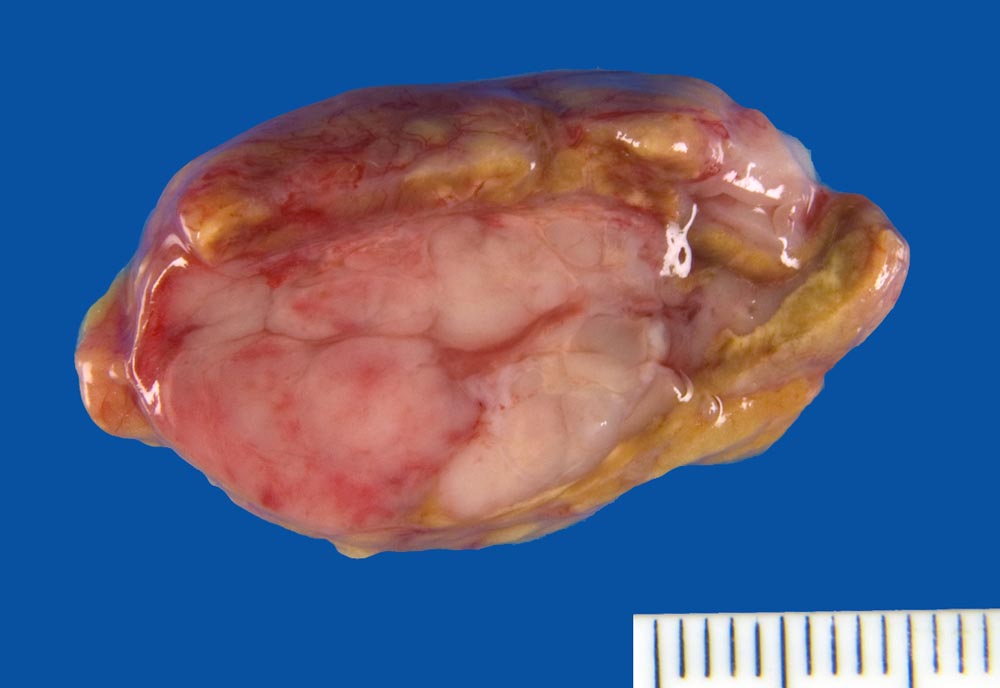

Makroskopisch sind die runden Osteolyseherde gefüllt mit einer weichen gelatinösen fischfleischartigen grauroten Tumormasse. Gelegentlich findet sich anstelle von Osteolysen eine diffuse Osteoporose. In der Knochenmarkbiopsie sind die Plasmazellen vermehrt. Im Gegensatz zu den kleinen Aggregaten von 5 bis 6 Plasmazellen rund um Markarteriolen bei reaktiver Plasmozytose bilden Plasmazellmyelome grössere Herde, Knoten oder flächenhafte Infiltrate. Für ein Plasmazellmyelom spricht eine tumorale Masse von Plasmazellen, welche das ortsständige Knochenmark verdrängt. Wenn über 10% des Markvolumens von klonalen Plasmazellen eingenommen wird, ist die Diagnose eines Plasmazellmyeloms sicher. Je nach klinischer Präsentation liegt dann eine symptomatische oder asymptomatische Verlaufsform vor. Die neoplastischen Zellen produzieren meist monotypische zytoplasmatische Ig (meist IgG, gelegentlich IgA, selten IgD, IgE oder IgM). 85% produzieren Schwerketten und Leichtketten, die restlichen 15% ausschliesslich kappa oder lambda Leichtketten (> 1097). Die klonalen Paraproteine können in den meisten Fällen mit einer Serumelektrophorese oder Urinelektrophorese gemessen werden können.

Makroskopie

Befund

Pathologischer Befund